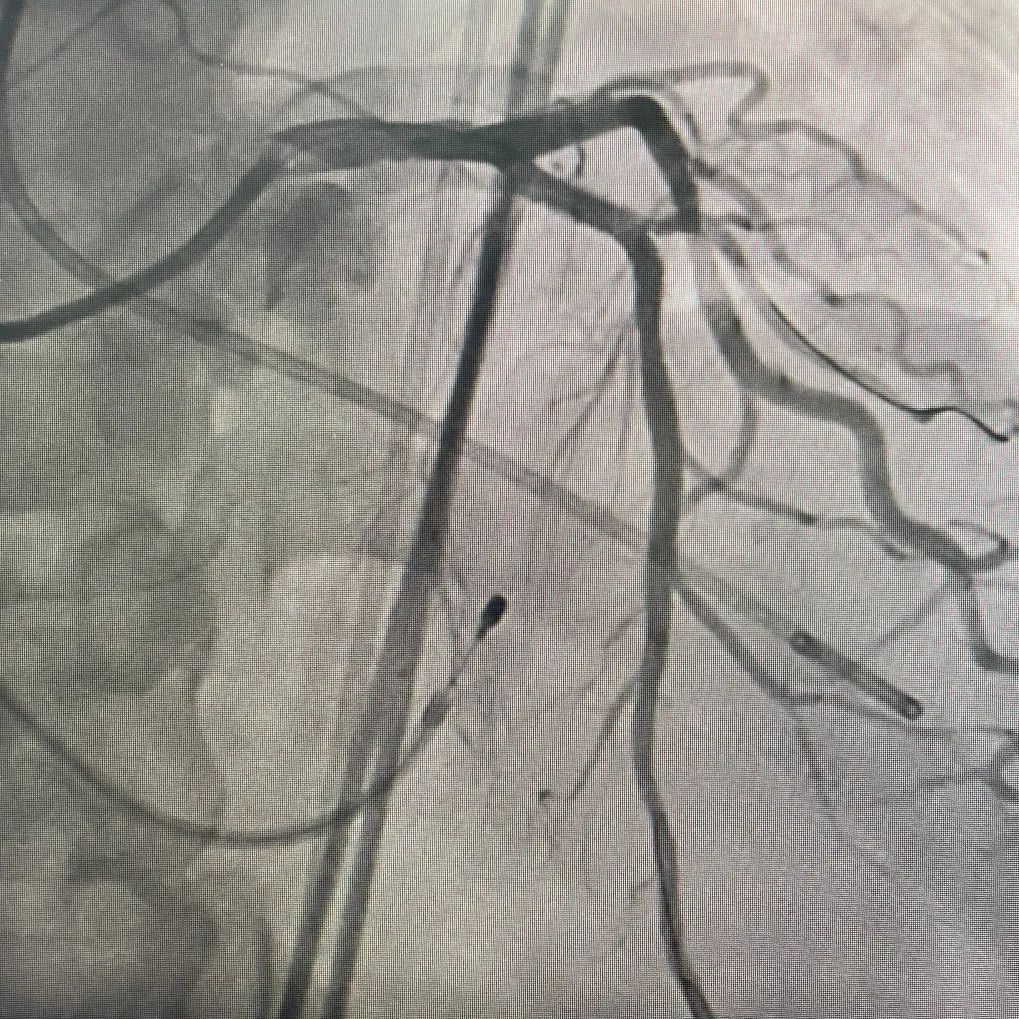

冠脉造影

冠脉硬化

LAD病变

冠脉处理前

冠脉处理后

冠脉处理前后对比